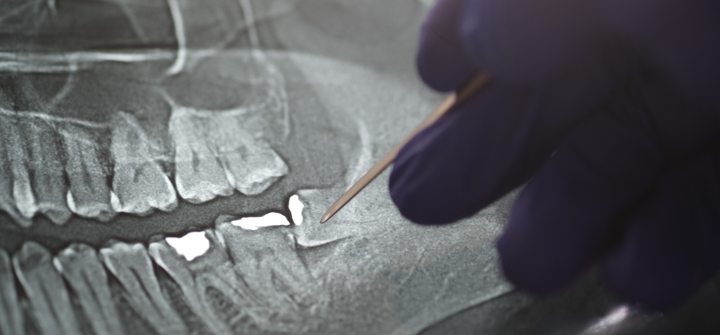

Panoramic Xray tooths showing Amalgam that used for dental restorative material

Image at top

Panoramic Xray shows amalgam used for dental restorative material. Istock/Getty